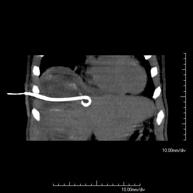

Consiste en colocar un catéter de drenaje sobre una colección líquida localizada en la cavidad abdominal, con la intención de vaciar el máximo posible dicha colección. El paciente deberá mantener el drenaje algunos días, normalmente hasta que no sea productivo. A menudo se realiza bajo sedación, con la ayuda del equipo de anestesia. Todo el procedimiento se realiza controlado con imágenes obtenidas por Tomografía Computarizada (TC) en varios momentos de la prueba mediante el empleo de Fluoroscopia-TC. Tras la prueba, el paciente permanece hospitalizado. Es necesario aportar pruebas de coagulación antes de la prueba.

Consisteix en col·locar un catèter de drenatge sobre una col·lecció líquida localitzada en la cavitat abdominal, amb la intenció de buidar el màxim possible d'aquesta col·lecció. El pacient haurà de mantenir el drenatge uns quants dies, normalment fins que no sigui productiu. Sovint es realitza sota sedació, amb l'ajuda de l'equip d'anestèsia. Tot el procediment es realitza controlat per imatges obtingudes per Tomografia Computaritzada (TC) en diversos moments de la prova mitjançant l'ús de Fluoroscòpia-TC. Després de la prova, el pacient resta hospitalitzat. És necessari que porti proves de coagulació abans de la punció. - Biòpsia òssia guiada per TC